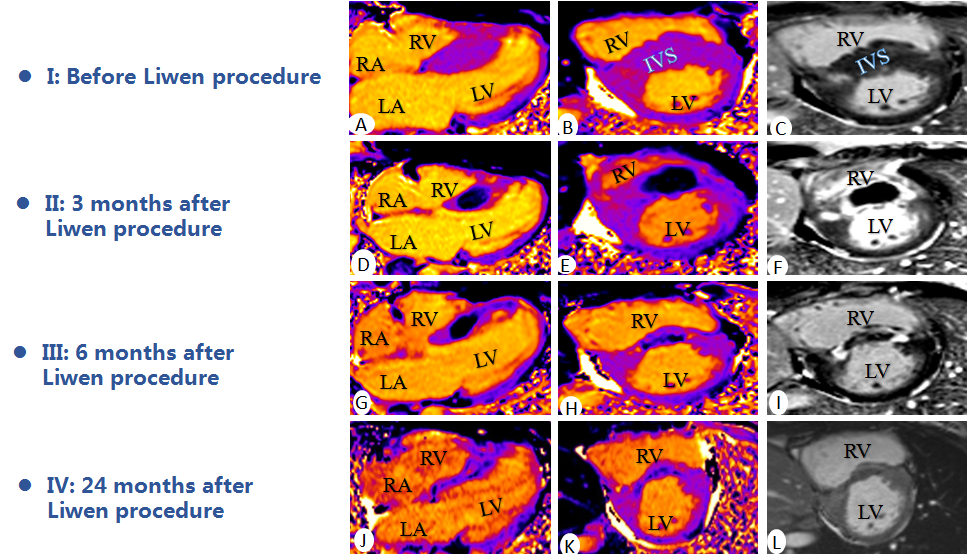

Liwen术式病例介绍

|作者:李静 刘丽文

|单位:空军(第四)军医大学西京医院